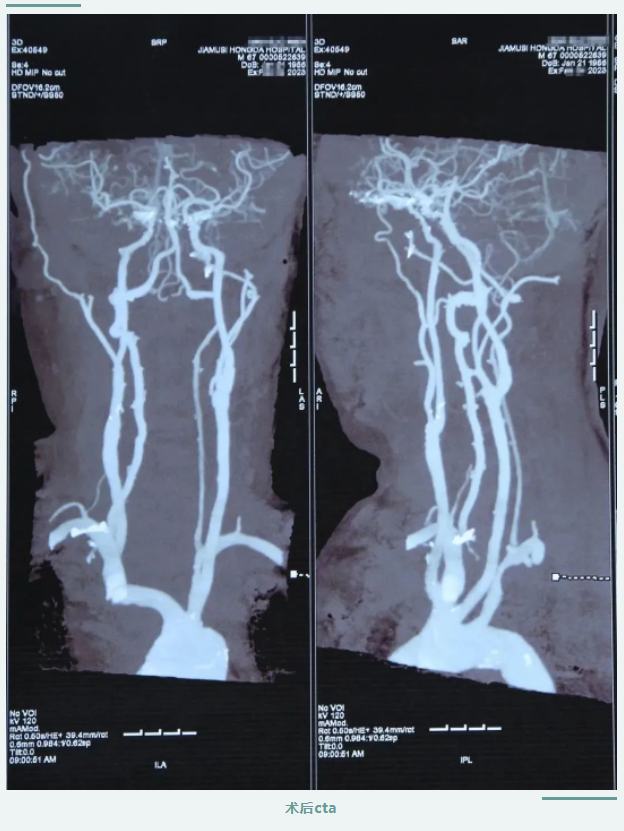

在醫(yī)護(hù)人員及患者家屬的精心照料下,患者術(shù)后狀態(tài)恢復(fù)良好,頭暈及肢體乏力明顯改善,肢體恢復(fù)知覺(jué)、可自主活動(dòng),言語(yǔ)清晰,感覺(jué)良好。

頸動(dòng)脈內(nèi)膜剝脫手術(shù)的順利完成,是我院在腦血管病治療中取得的新突破,填補(bǔ)了我院頸動(dòng)脈剝脫手術(shù)技術(shù)空白,對(duì)于腦卒中的預(yù)防和治療具有重要作用,標(biāo)志著我院腦血管病診療技術(shù)再上新臺(tái)階。